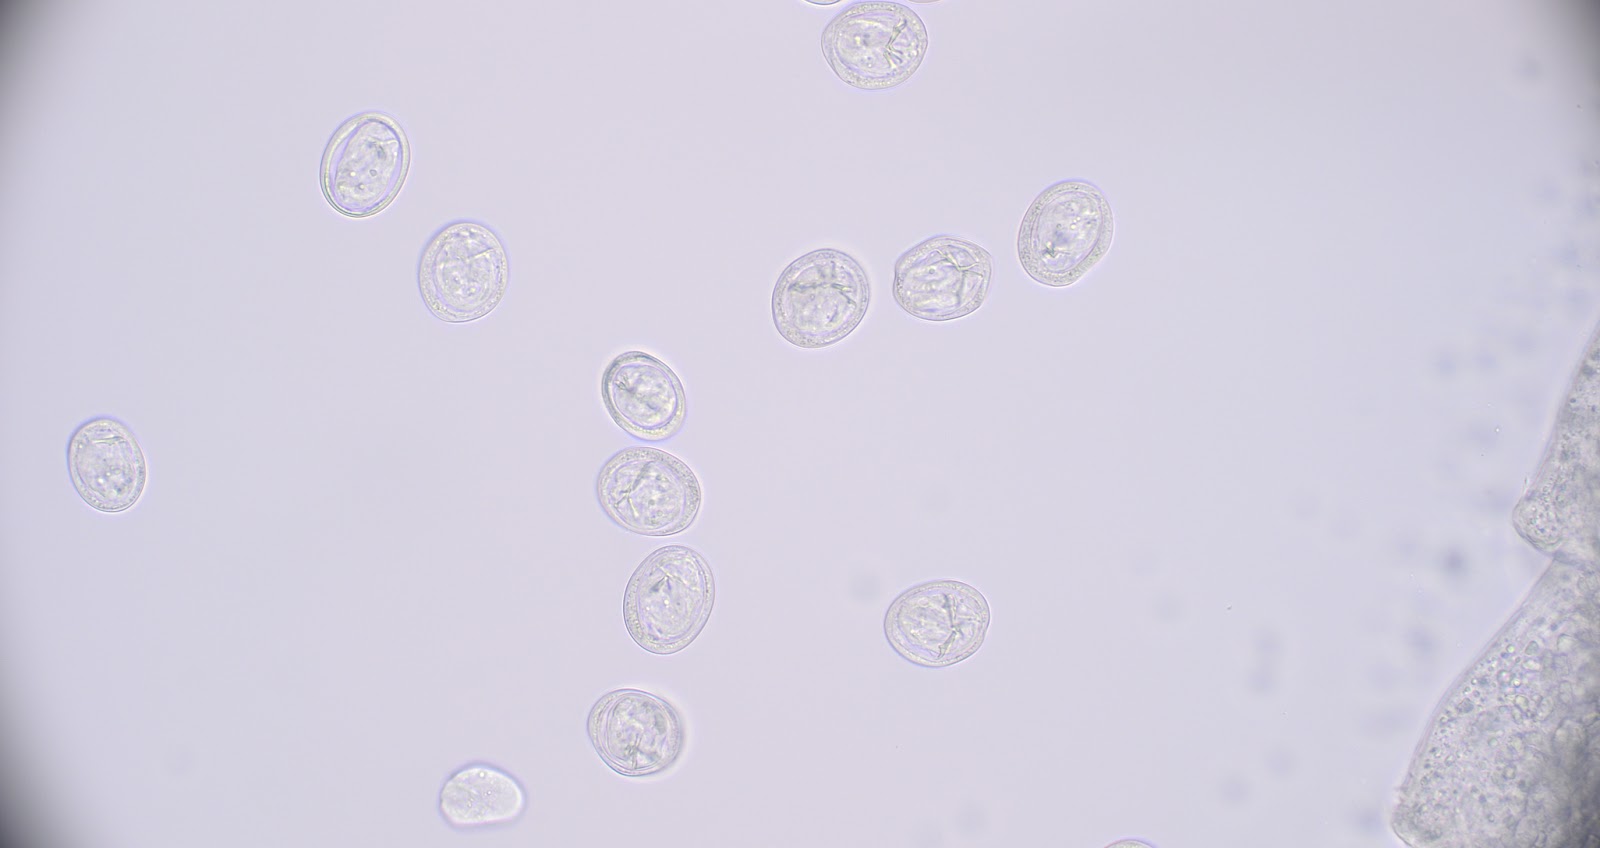

Case of the Week 788

Happy Autumn, everyone! It's the first Monday of the month and time for our monthly case from Idzi Potters and the Institute of Tropical Medicine, Antwerp. The following were seen in a direct wet mount specimen of stool from a patient with chronic constipation. What is your identification?

Answer to Case 788

Answer to Parasite Case of the Week 788: Pentatrichomonas hominis trophozoites

Note the classic 'jerky' motility of P. hominis trophozoites. I've never seen so many P. hominis in a specimen before!

Like Trichomonas vaginalis, there is no known cyst stage of this protozoan parasite. P. hominis trophozoites move using 5 flagella: 4 are directed anteriorly, while the 5th is directed posteriorly, forming the outer edge of an undulating membrane. This results in characteristic motility that Dr. Richard Bradbury likes to describe as "a man trapped inside a plastic bag"! You can see a very nice video and still images of this phenomenon in Case of the Week 737. For those of you who have been following this blog since the beginning (2007!), you may recall that P. hominis was the parasite highlighted in Case of the Week 5. Check out the fun video that Alex Ball made for me back then in the Answer to the Case of the Week 5.